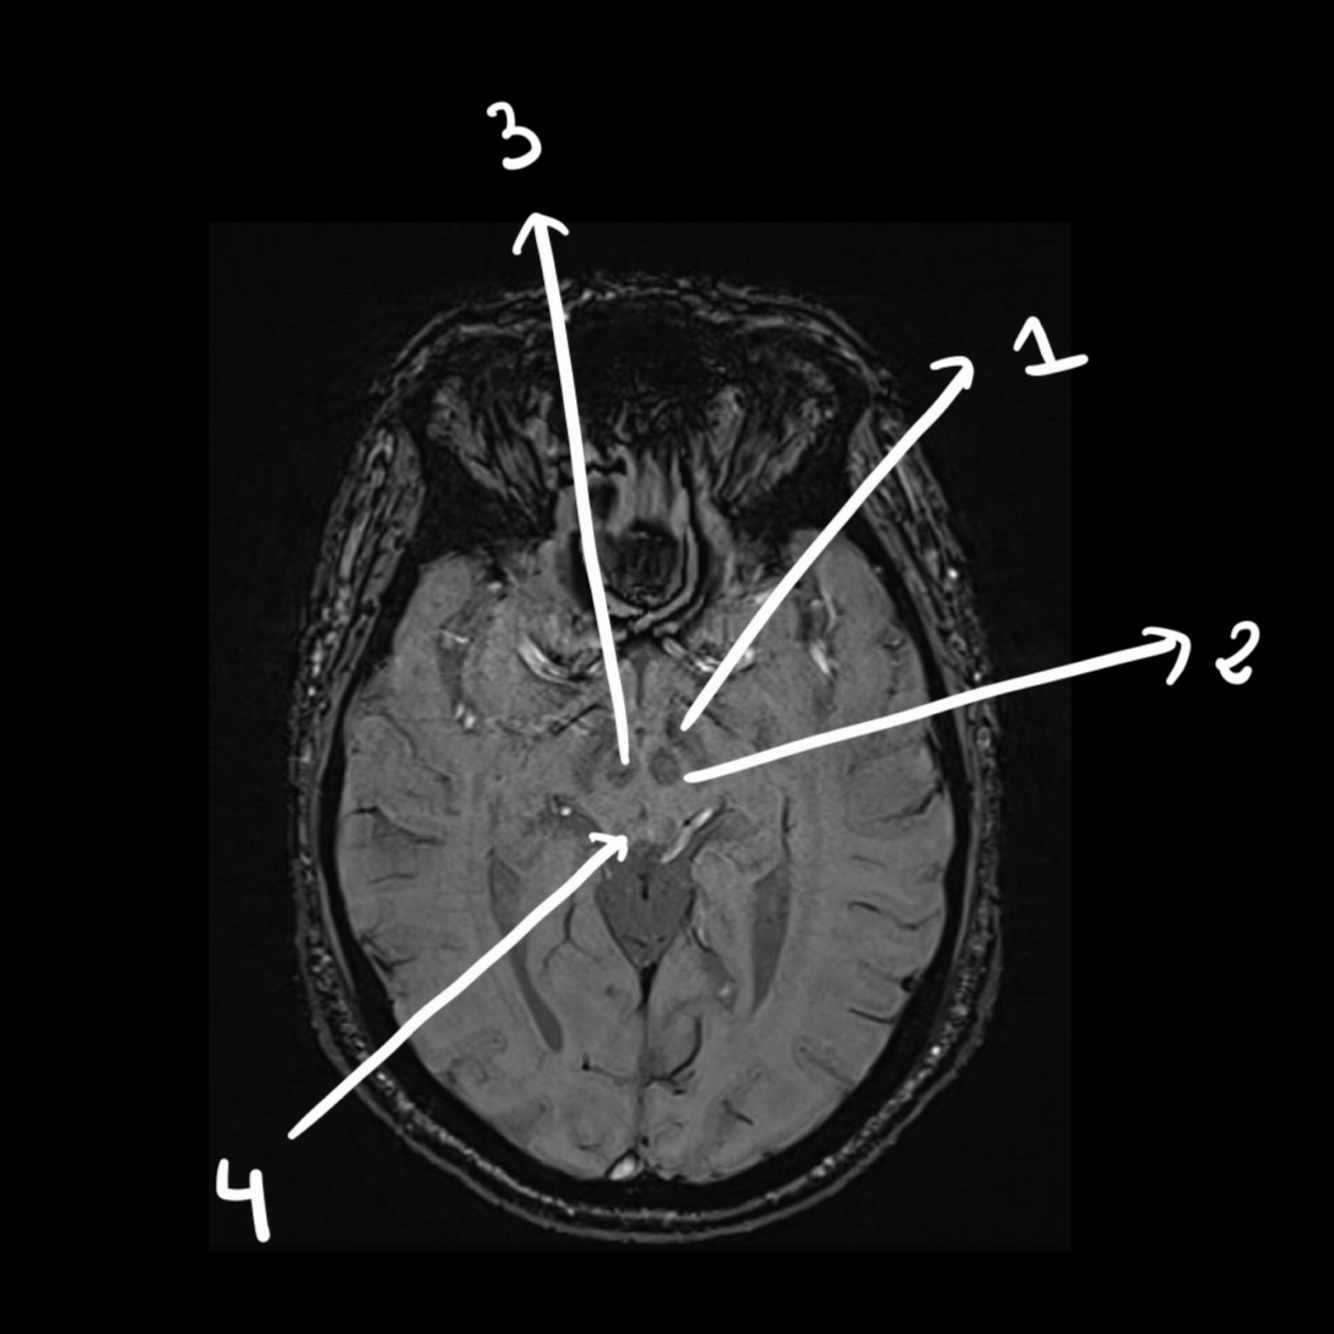

Normally, we use contrast in the brain (T/F)

FALSE: it stays the same after contrast

Only pituitary glands and vessels enhance